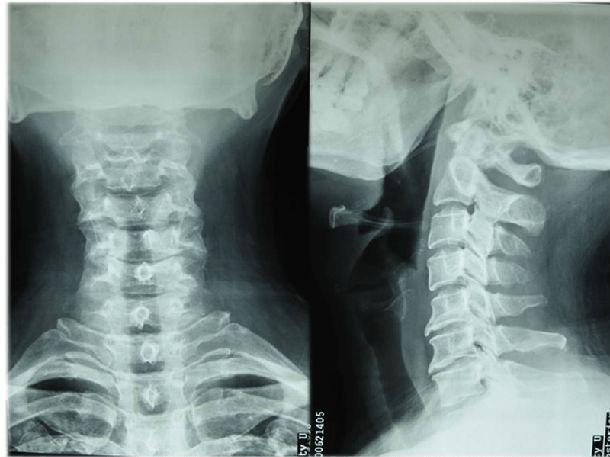

颈椎正侧位

颈椎正侧位,颈椎正侧位报告模板

术前颈椎正侧位片,见颈椎蜕变,局部骨质增生.

颈椎正侧位片

颈椎正侧位x光片

1. 颈椎的生理曲度 正常人的侧位片可见颈椎生理性 前凸.